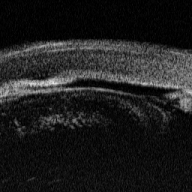

глаукомой и у 5 - со вторичной глаукомой. В качестве примера приводим УБМ

больного Ч. с первичной закрытоугольной глаукомой (рис. 3) и больного К. с

оперированной закрытоугольной глаукомой (рис. 4).

Рис. 4 - УБМ переднего отрезка глаза больной К.

Щелевидная передняя камера, обширная передняя синехия, отек роговицы

У обоих пациентов при гониоскопии выявлен

закрытый УПК. Однако ультразвуковая биомикроскопия показала, что у больного Ч.

причиной закрытия УПК являлось переднее прикрепление радужки, а у пациента К. -

круговая гониосинехия, закрывающая УПК. В обоих случаях не дифференцируется

склеральная шпора (рис. 5), которая является основной контрольной точкой для

количественного анализа УБМ-изображений структур УПК [3, 5].